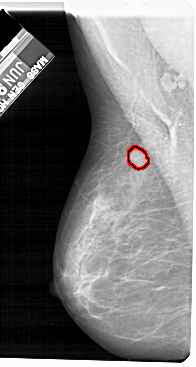

FILE: A_1524_1.LEFT_MLO.OVERLAY

TOTAL_ABNORMALITIES 1

ABNORMALITY 1

LESION_TYPE MASS SHAPE OVAL MARGINS ILL_DEFINED

ASSESSMENT 4

SUBTLETY 2

PATHOLOGY BENIGN

TOTAL_OUTLINES 1

BOUNDARY